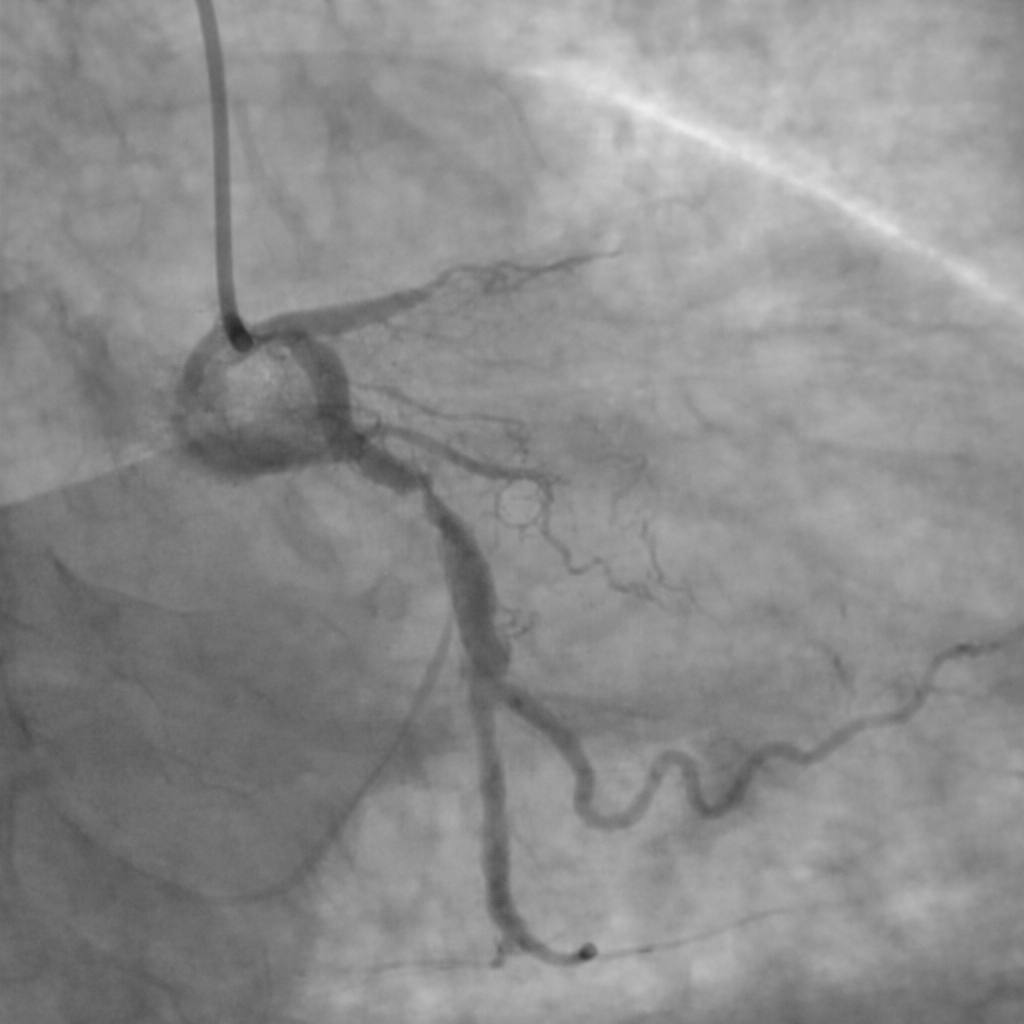

Stenturile se pot înfunda”, subliniază dr. Țoni Ovidiu. Acesta prezintă cazul unui pacient prezentat recent cu infarct miocardic acut, deși avea stenturi implantate de mai mulți ani.

Specialistul explică faptul că, în astfel de situații, apare sternoza intrastent, o îngustare a arterei în interiorul stentului, fenomen care poate fi provocat fie de proliferarea țesutului, fie de tromboza de stent, favorizată direct de întreruperea tratamentului antiagregant.